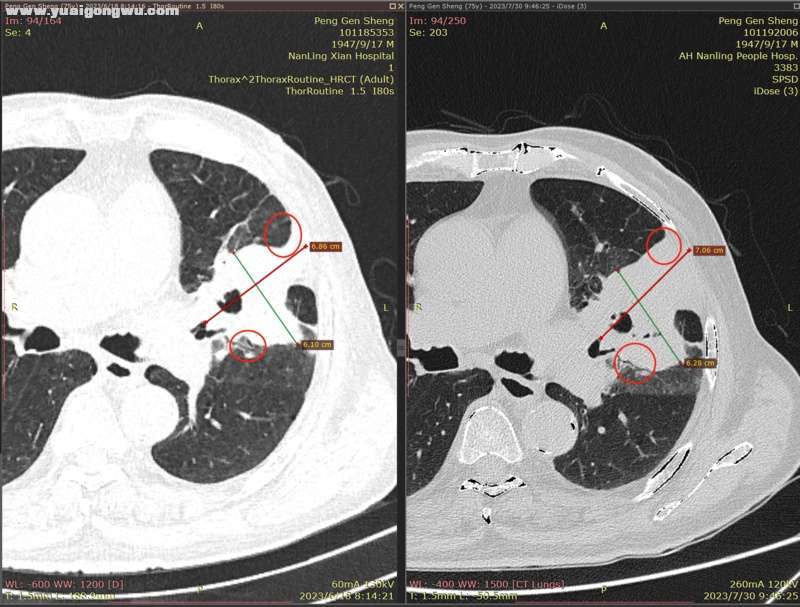

6月3日~7月29日,单用安罗替尼12mg(3周期),6月18日CT显示左肺主病灶稍缩(主病灶62mmx57mm);因近期有一点点吸不上气的感觉(吸氧后有缓解,其他身体体征正常,体感良好),7月30日CT显示左肺主病灶稍增大(主病灶68mmx62mm)。- L* L' w9 C: J7 b

影像科医生将7月30日的胸部CT,和6月18日的胸部CT电子影像对比分析如下:

: v& _. J  {' _( E1 `) |4 A: L* ^         1、左肺上叶主病灶(肿块),7月30日复查较2023.6.18略增大,如图红圈所示,局部边缘饱满(图1);: O% K* B! J8 F9 Q9 t8 j3 d

3、右肺中叶实变区域,体积略变小(图6);- z3 W  \% n% e

* R5 w. e) k/ [9 Y( L' s' h* x* n7 d        以下为近两次CT影像的对比分析。7 Z8 B" @7 n7 B# ?+ K" ?( E( {) v